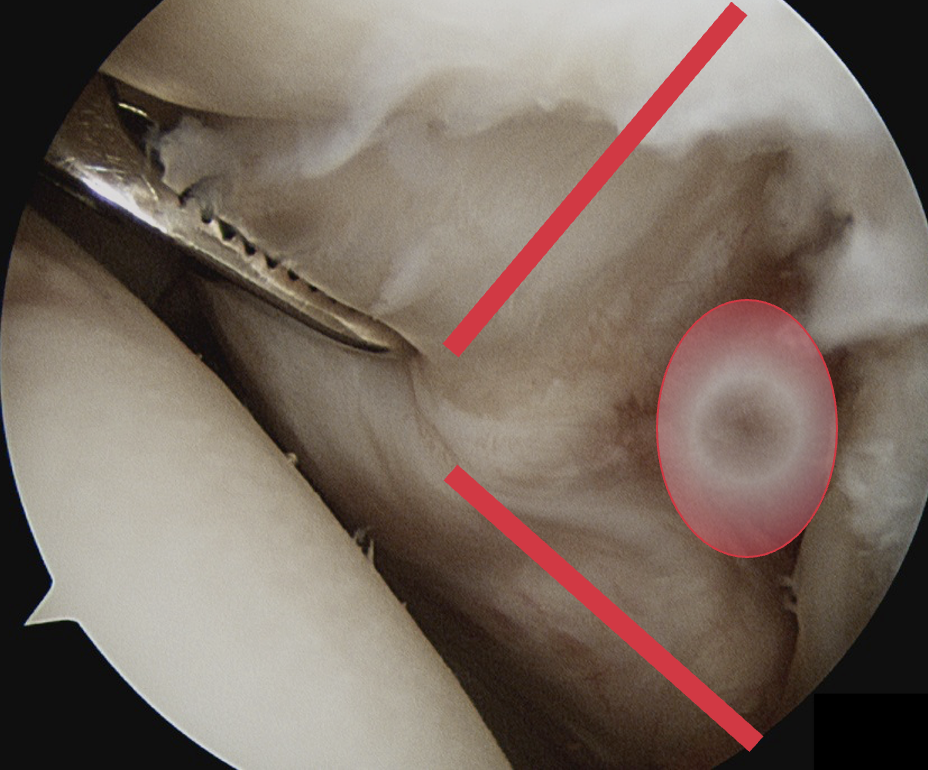

Comma sign

- medially retracted subscapularis tear

- exposes the superior insertion of superior glenohumeral ligament / coracohumeral ligament

Full thickness completely retracted subscapularis, loss of rotator interval and comma sign